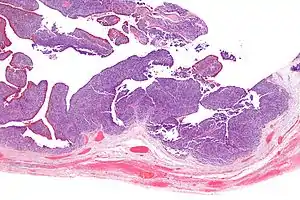

| Micrograph of transitional cell carcinoma of the ovary. H&E stain. |

TCC of the ovary is diagnosed by examination of the tissue by a pathologist. It has a characteristic appearance under the microscope and distinctive pattern of immunostaining.[2]